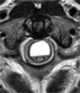

Syringobulbia

Syringobulbia is a medical condition in which syrinxes, or fluid-filled cavities, affect the brainstem. This defect normally results from congenital abnormality, trauma or tumor growth. [Source: Wikipedia ]